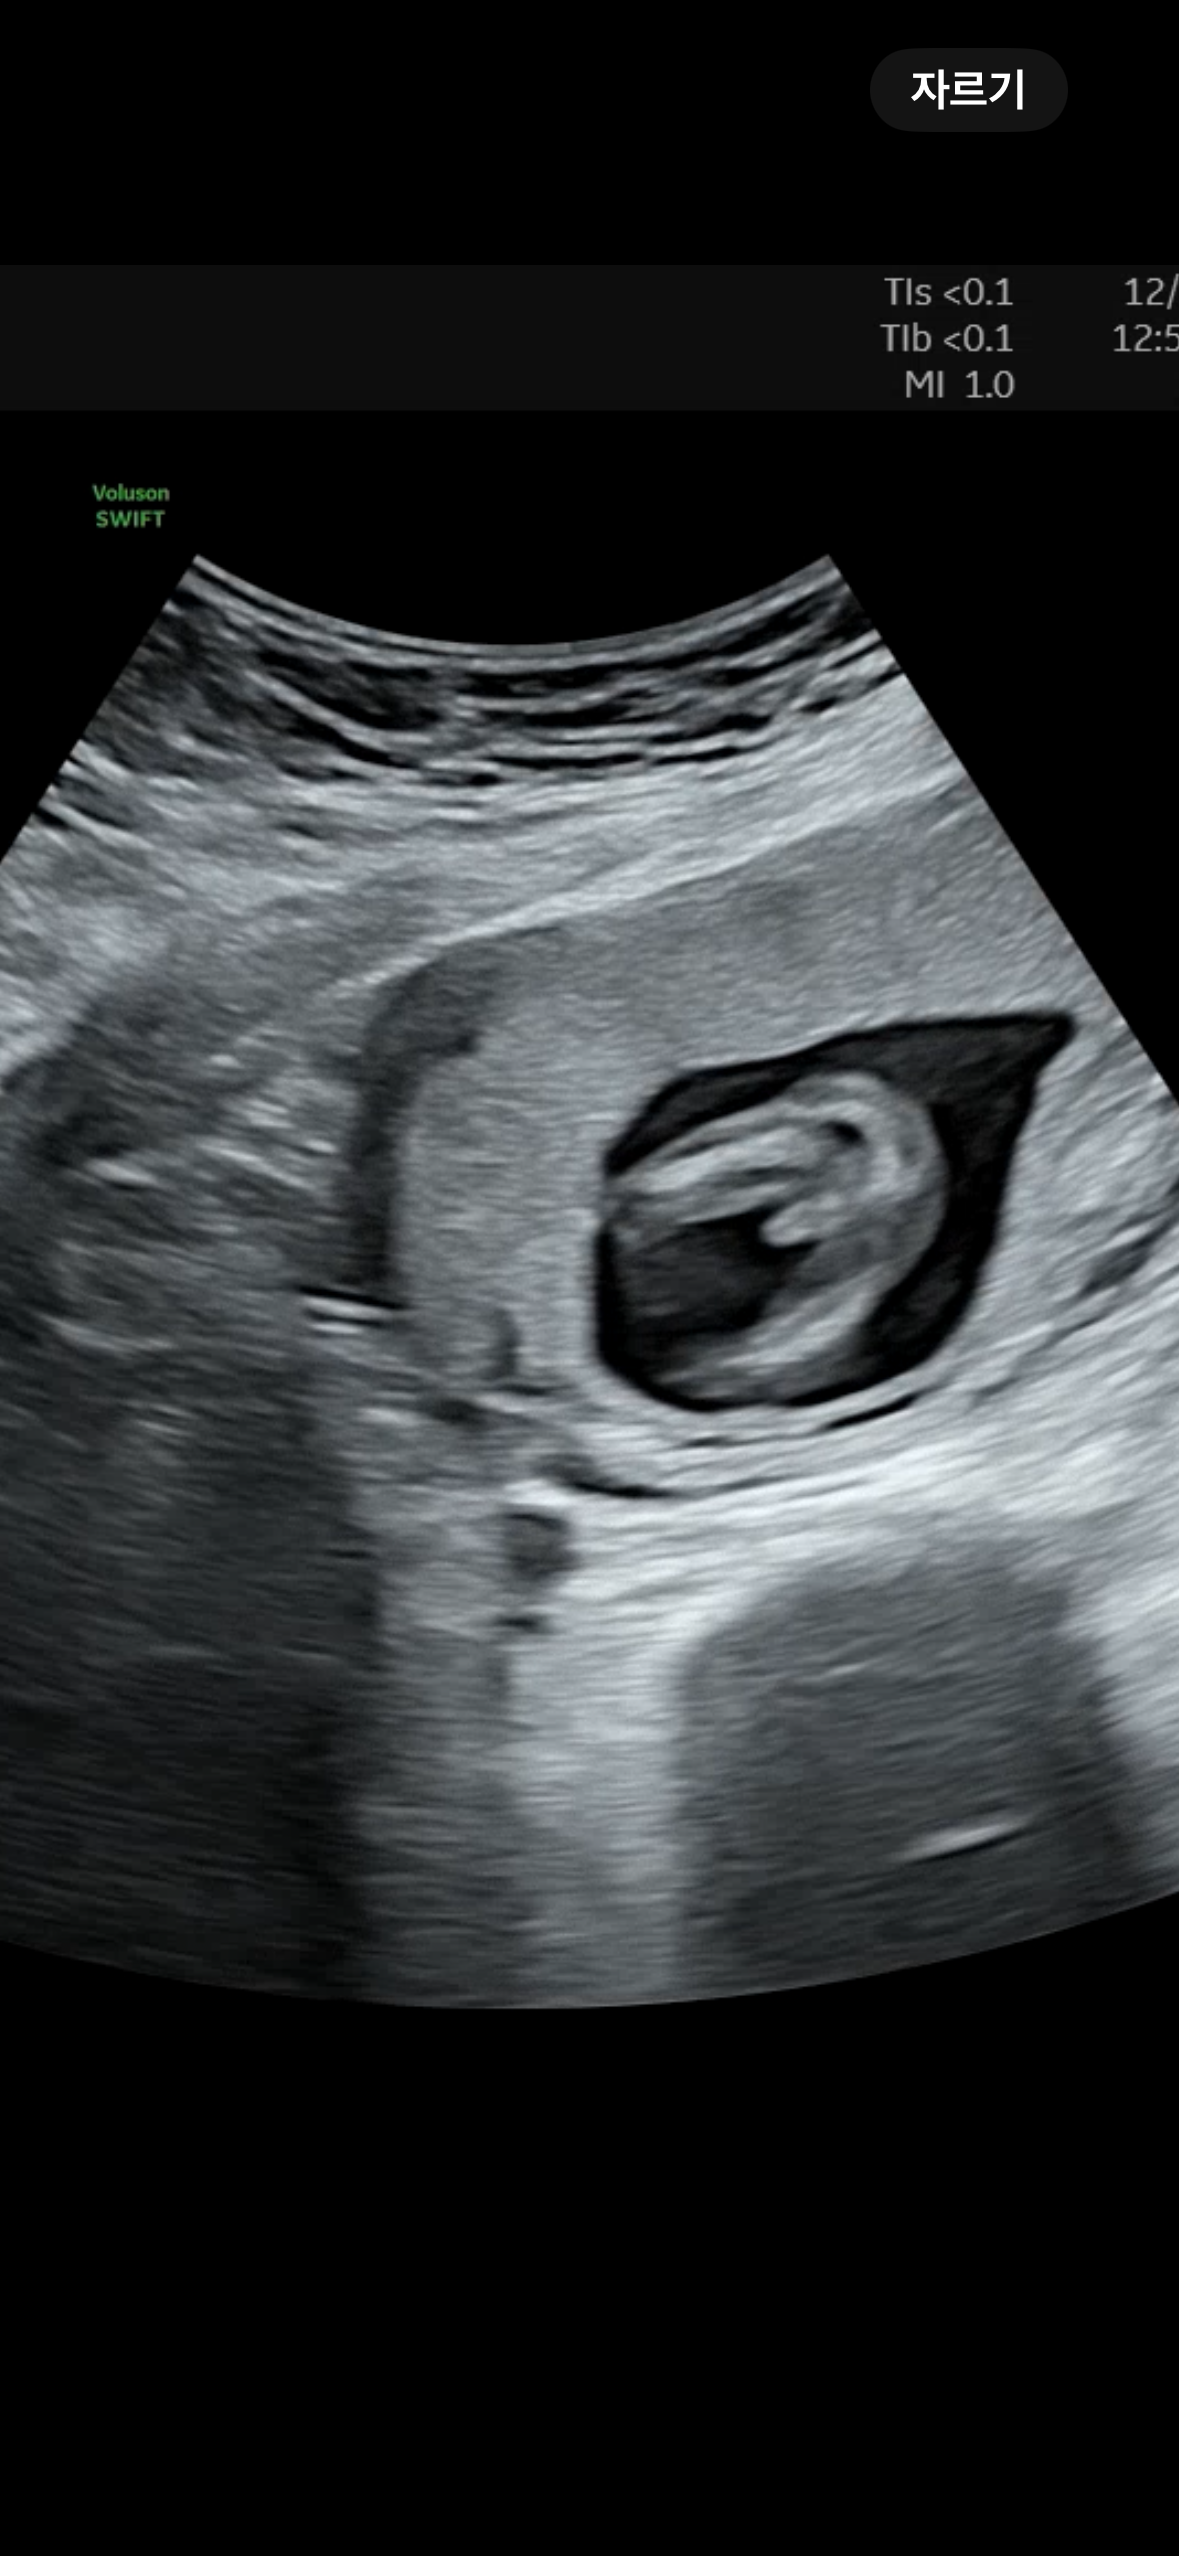

14주2일차 아들 확정일까요?

의사선생님은 백프로 확정은 아니라고 하셨는데 이정도면 확정일까요??😂

탯줄 아니라면.. 저정도면 아들 빼박인듯 해요 ㅋㅋㅋ 저두 14주 차에 저렇게 보였는데, 16주 되자마자 갔더니 아들이래요